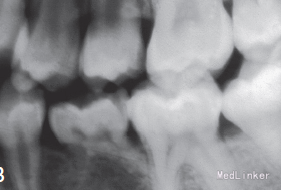

左下第二乳磨牙滞留,上下牙列轻度拥挤不齐.全景示左下第二乳磨牙无相应的恒牙,先天缺失35牙

诊断:35牙缺失,牙列不齐 治疗:排齐整平上下牙列,对滞留的乳磨牙处理如下:因乳磨牙宽大,较正常前磨牙近远中径大很多,正畸治疗过程中逐次给乳磨牙减径后树脂修复参与正畸治疗,使减径树脂修复后的乳磨牙宽度为以后修复的前磨牙宽度一致。减径后的间隙留作牙列内其他牙齿的排齐。